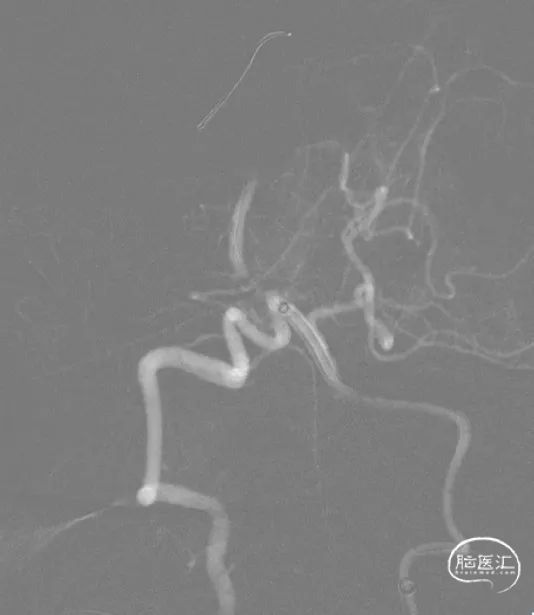

脑血管造影:显示基底动脉闭塞。

DSA显示基底动脉闭塞。

DSA,LVA

左侧椎动脉迂曲,应用6F长鞘加5F支撑导管提供更好支撑及更高到位。

微导丝微导管引导下支撑导管到位。

微导管越过闭塞段冒烟显示远端血管真腔。

抽吸后显示的基底动脉近端重度狭窄。

球囊扩张后,支撑导管越过闭塞段抽吸远端血栓。

支架到达狭窄部位。

赛诺神畅 颅内药物洗脱支架NOVA DES®2.25*15mm植入后。

1.术中定位精准,避免支架覆盖远端PICA;

2.易损斑块,球扩支架避免了反复扩张导致斑块脱落风险;

3. 赛诺神畅 颅内药物洗脱支架NOVA DES®整体通过性较好,在严重迂曲血管中推送可应用远端支撑导管,以利于支架更好到位。

4.良好径向支撑力可有效预防斑块回弹导致再狭窄;

5.药物涂层可显著降低后期再狭窄几率?期待后期随访。